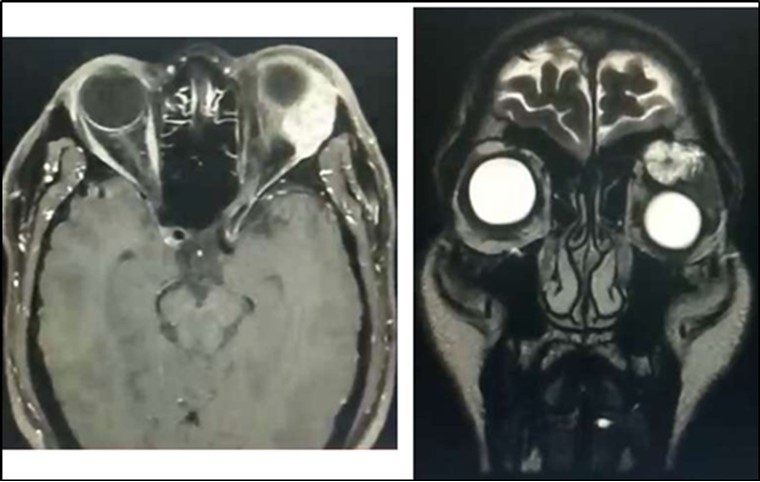

Orbital MRI showed a 2.6 x 2.9 x 3.2 cm (cc x w x ap) heterogeneously enhancing mass seen in the extraconal space (superolateral aspect) likely arising from the left lacrimal gland (Figure 2). The lesion exhibits mixed (predominantly hyperintense T2 wave and predominantly intermediate T1W) signals. Mass effect was noted compressing the retrobulbar fat with resultant medial displacement of the optic nerve, inferior displacement and anterior protrusion of the globe. The mass abuts the superior rectus, levator palpebrae superioris and lateral rectus muscle.

Figure 2.Orbital MRI showing an enhancing lacrimal gland mass (Axial & Coronal Views), left